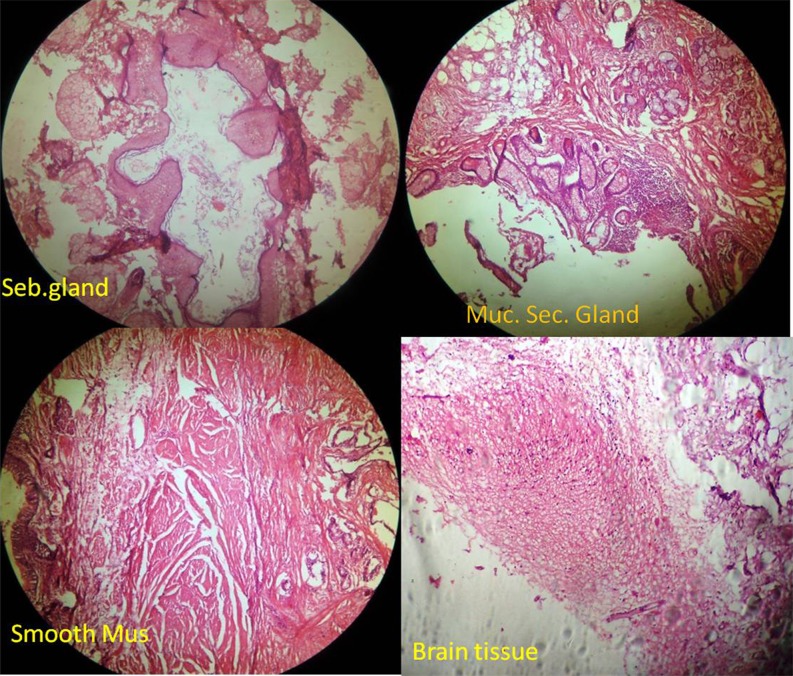

A 21-year-old male patient presented with history of persistent productive cough and dyspnea for 1.5-month duration. Physical examination showed decreased air entry on the right side in infraclavicular, mammary, and infra-axillary areas. Chest X-ray (Fig. 1) showed a mediastinal mass and collapse of the right lung. CT scan of chest (Fig. 2) showed a large heterogeneous soft-tissue dense mass of 13.6 cm × 11.1 cm in the anterior mediastinum extending to right hemithorax with areas of fat and calcification within the lesion. The mass was compressing the cardia and great vessels of the mediastinum and the right middle and lower lobe bronchi; mild atelectasis of the right middle lobe was noted. Fat planes with pericardium were obliterated. USG-guided fine-needle aspiration cytology revealed a benign cystic teratoma. Testicular ultrasonography showed both the testes to be normal. The patient was planned for complete resection. He underwent a right anterolateral thoracotomy through the 5th intercostal space. Intraoperatively a large mass of 12 cm × 10 cm × 8 cm present in right hemithorax, anterior to hilum of the right lung (Fig. 3). Mass, was adherent anteriorly to the chest wall, medially to pericardial fat, and inferiorly and posteriorly to the lung tissue. With careful blunt and sharp dissection, the mass was dissected all around and was resected completely without injuring any vital structures. Apical and basal thoracostomy tubes were placed and wound was closed in layers. Post-excision lung expansion was 80 % intraoperatively. Postoperative period was uneventful. Serial postoperative X-rays showed good right lung expansion (Fig. 4). Grossly cut section showed pultaceous material, hairs, cartilage, bone and teeth (Fig. 5). Microscopy revealed a mature teratoma with cystic structures lined by stratified squamous epithelium and at places cartilage, bone, respiratory epithelium, mucous secreting glands, adipose tissue, and brain tissue (Fig. 6)

Fig. 6.

Microscopic picture